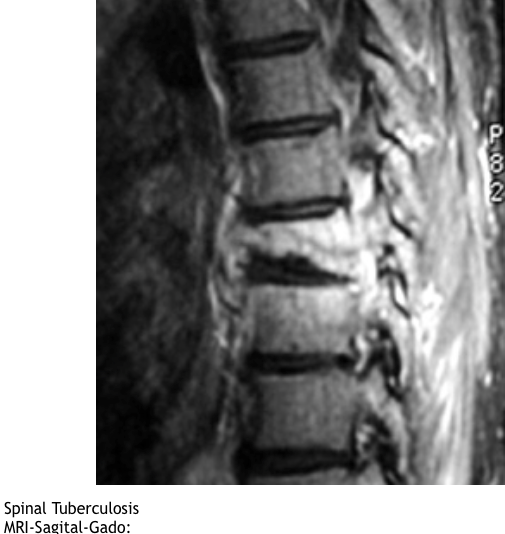

What is the epidemiology of spinal TB ?

location

What is the pathoanatomy of spinal TB?